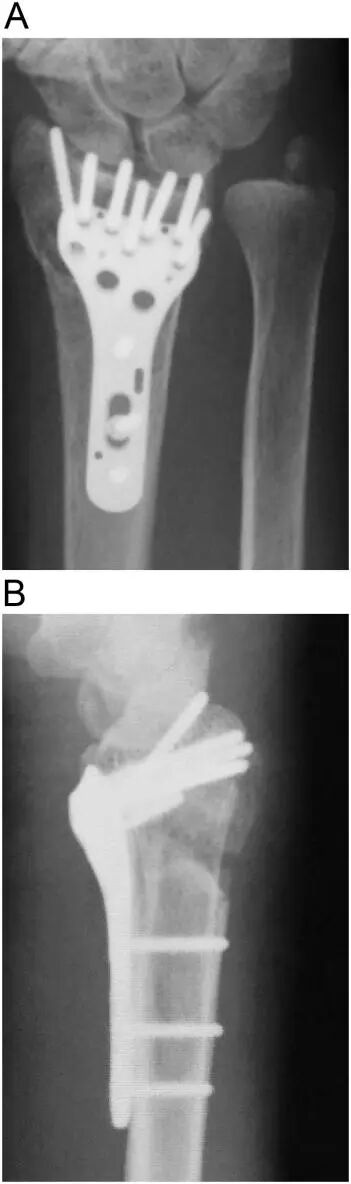

图2:术中C臂透视显示螺钉固定情况,尤其关注远端螺钉穿透背侧皮质以固定背内侧碎片。此图可能清晰显示了螺钉的长度和其与背侧皮质的关系,证实螺钉已穿透背侧皮质并突出。 -

此图可能为术后影像学检查,显示骨折复位良好,钢板和螺钉位置稳定,同时展示了突出螺钉在第三隔室中的情况,以及EPL肌腱已被安全处理后的良好效果。 - 在此病例中,手术进行至螺钉固定后,通过背侧小切口打开第三隔室。由于螺钉已穿透第三隔室并突出,我们按照上述方法将EPL肌腱从其凹槽中取出并通过缝合支持带来关闭隔室,确保肌腱远离螺钉,避免摩擦。